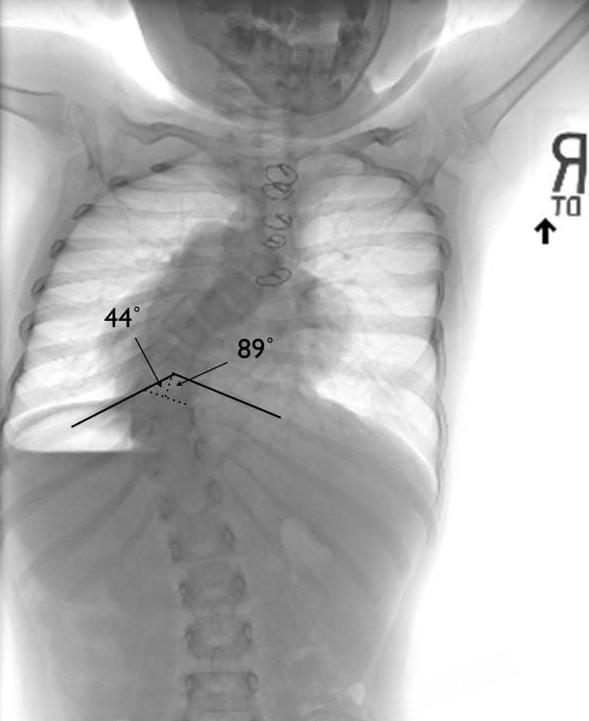

脊柱变形的影响远不止是外形上的改变。研究发现,如果在生长发育期出现明显的脊柱弯曲或畸形,会对胸腔和肺部的发育造成长期影响,容易引发"胸廓功能不足",从而导致呼吸困难或肺功能下降 [ 8 ] 。此外,脊柱畸形还会影响身高的正常增长,出现身材矮小或生长受限的情况 [ 9 ] 。

x 光片显示,患者由于脊柱变形,对肺部造成了压迫 / [ 8 ]